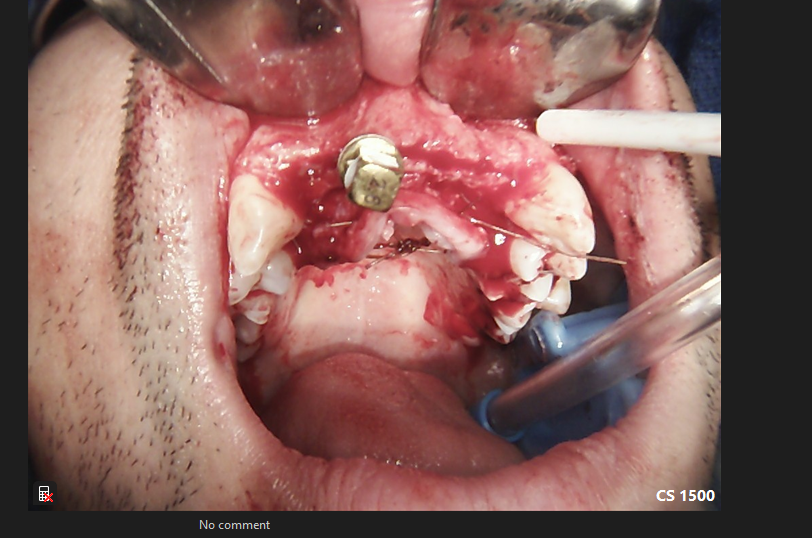

Narrow Anterior Maxillary Ridge Expansion Grafting